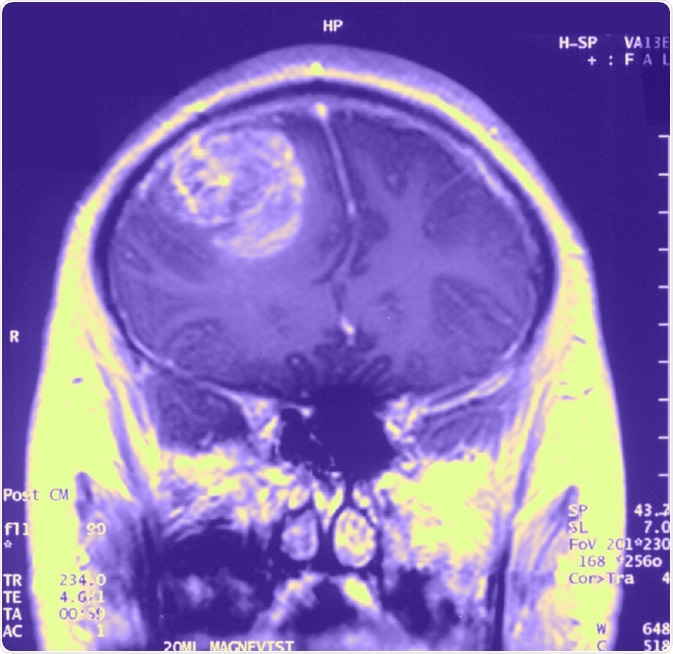

Gliobastoma (astrocytoma) WHO grade IV - MRI coronal view, post contrast. 15 year old boy. image Credit: Christaras A

Diagnosis is usually made by performing neuroimaging to localize the tumour. These tools include CT scans, PET scans and MRI scans. Once a tumour has been located, a biopsy is taken through a craniotomy for definitive diagnosis.